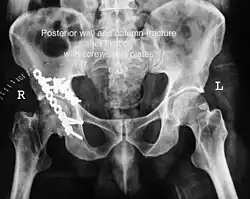

Acetabular fracture as seen on plain X-ray

Posterior wall This is the most common variety of acetabular fracture. It typically occurs due to dashboard injury; when a person travelling in a vehicle involved in a head-on collision, the force applied over the flexed knee travels along the femur bone to the head of the femur, breaking the posterior wall of the acetabulum. The head of the femur is dislocated outside the joint. T shape When a transverse fracture also had a vertical fracture line, it is called a T shape fracture. Here the innominate bone is broken in such a way that all three parts of it, the ilium, the ischium and the pubis are separated from one another. This is a three part fracture. Though both columns are broken, the weight bearing dome is still attached to the main part of the ilium and hence it is not a true fracture of both columns.

Posterior column As with posterior wall injury, this also typically occurs due to dash board injury. Posterior column + Posterior wall These fractures are extensions of elementary fractures. With the involvement of the posterior wall, the difficulty in treatment increases. These fractures are rarely amenable to non-surgical treatment. Due to posterior wall fracture, the hip is usually dislocated posteriorly, requiring immediate reduction of dislocation and surgical reconstruction after a few days.

• Posterior wall fracture: Iliac oblique and obturator oblique views

• Posterior column fracture: Iliac oblique and obturator oblique views